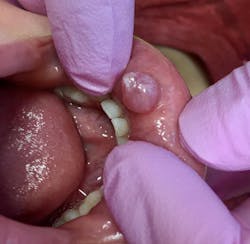

At a six-month checkup, the patient's chief complaint was a large sore on the lower lip that was described as: “comes and goes.” His mom said: "He will bite the bubble and it pops with lots of liquid, but it grows again."

- 7 mm-plus soft, exophytic, dome-like lesion

- Normal lip color

- Fluid filled with a slightly red base

The likely diagnosis in this case is oral mucocele, aka mucous retention cyst, from a blocked duct, secondary to chronic lip biting. It is hoped that the patient will eventually have a biopsy so a definitive diagnosis can be rendered. The patient's mom has been advised to be diligent in reminding her son to cease biting his lip.